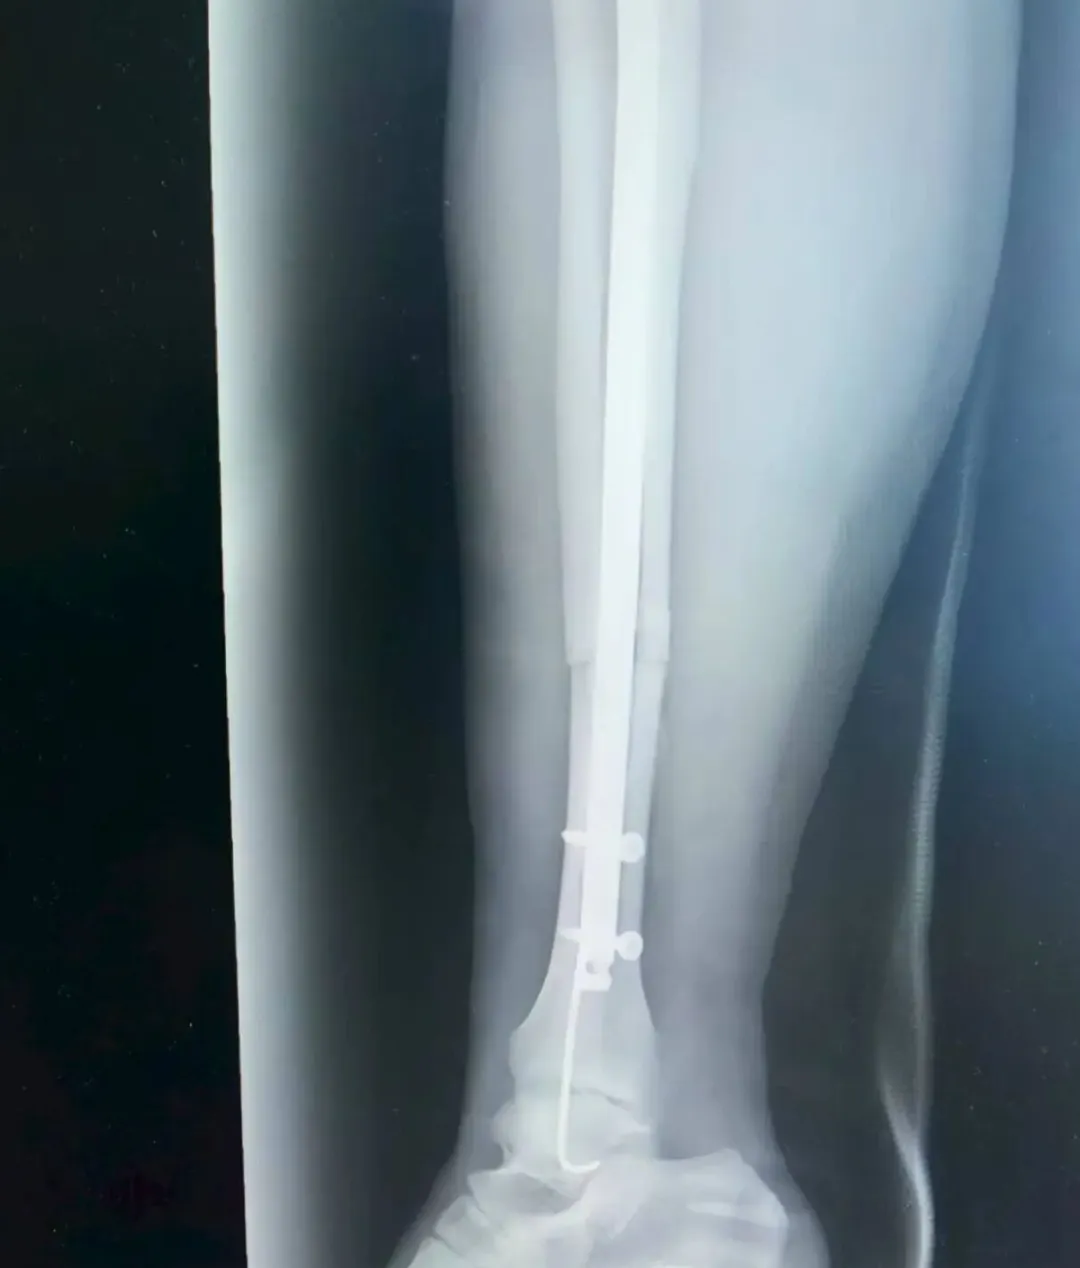

考虑到张女士是外地游客,不仅希望骨折能精准复位,还盼着创伤小、恢复快,不耽误后续返程与康复。董伟副主任医师结合影像学资料,综合考虑张女士的身体状况与个人需求,最终确定采用“胫腓骨骨折闭合复位+胫骨髓内钉内固定术+腓骨髓内针内固定术”,全程无需做大切口,通过微创方式实现骨折端精准对位,既能最大程度保护肿胀的软组织,又能显著提升术后恢复速度。

手术由董伟、孙毅珲共同完成,术中借助C臂机实时透视引导,小心翼翼地通过闭合复位技术调整骨折端位置,确保达到解剖复位标准;随后精准植入胫骨髓内钉与腓骨髓内针,完成固定。整个手术过程出血少,术后仅留下几个微小创口,最大程度减少了张女士的痛苦。